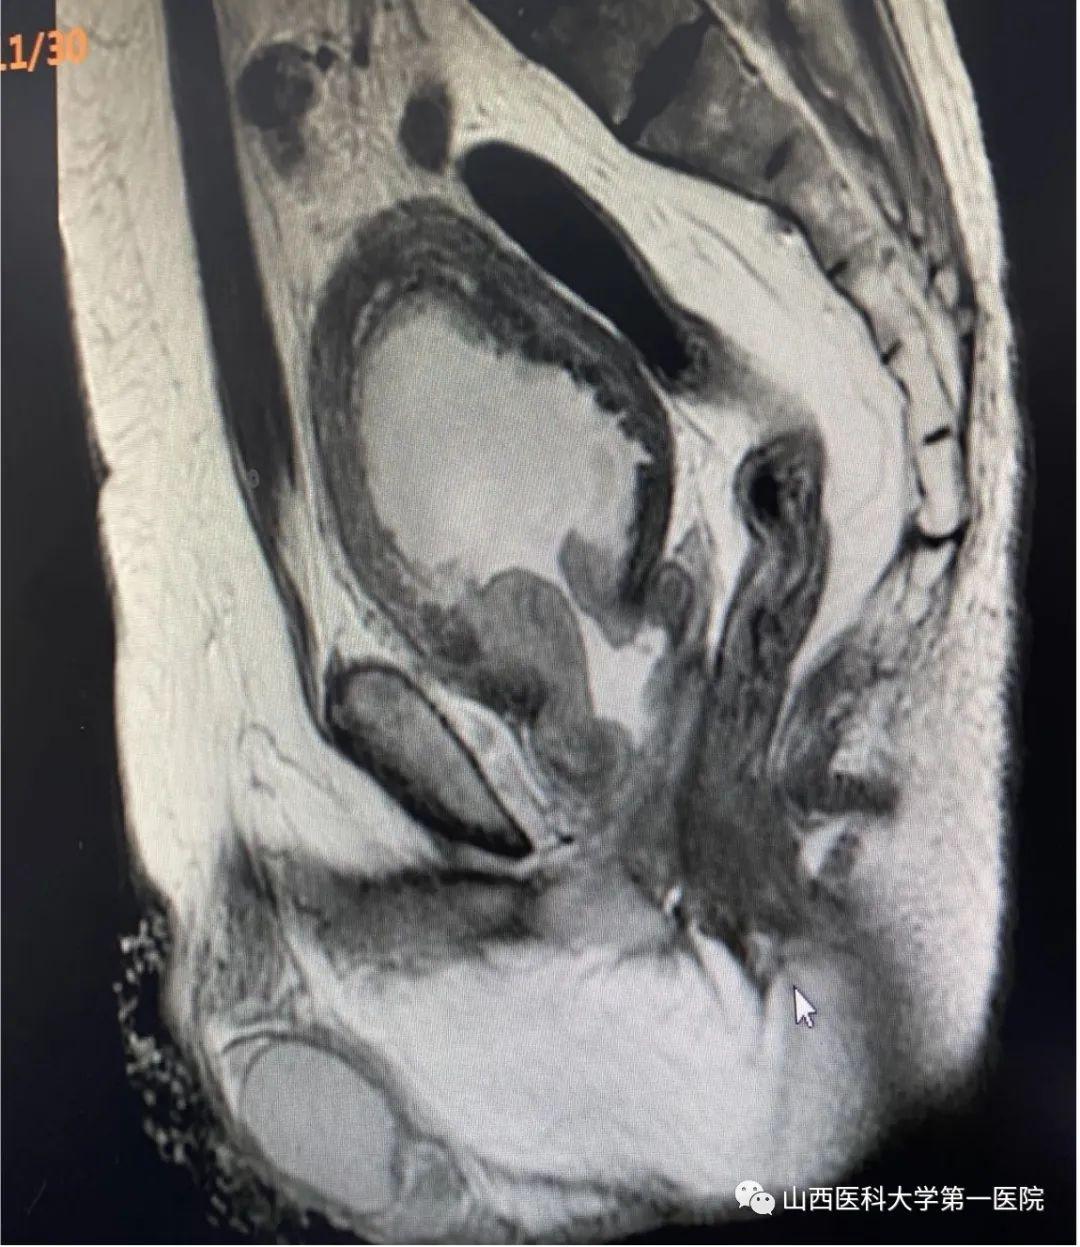

该患者为70岁老年男性患者,以尿频、漏尿为主要症状,长期排尿困难,夜不能寐,10年前曾出现过无法自主排尿,留置尿管病史。尹楠副主任医师详细询问病史及查体后,考虑患者为充盈性尿失禁,收治入院并完善泌尿系彩超检查后结果显示:前列腺左右径7.5cm,前后径12.6cm,上下径11.8cm,残余尿769ml,双肾积水,前列腺估重580g(正常人约为8-20g)。

由于患者前列腺极其巨大,全国少见,泌尿外科前列腺增生亚专业团队详细分析了前列腺形态,评估了膀胱功能并与患者及其家属沟通手术方案后,终决定了实施经尿道铥激光解剖性前列腺剜除术。